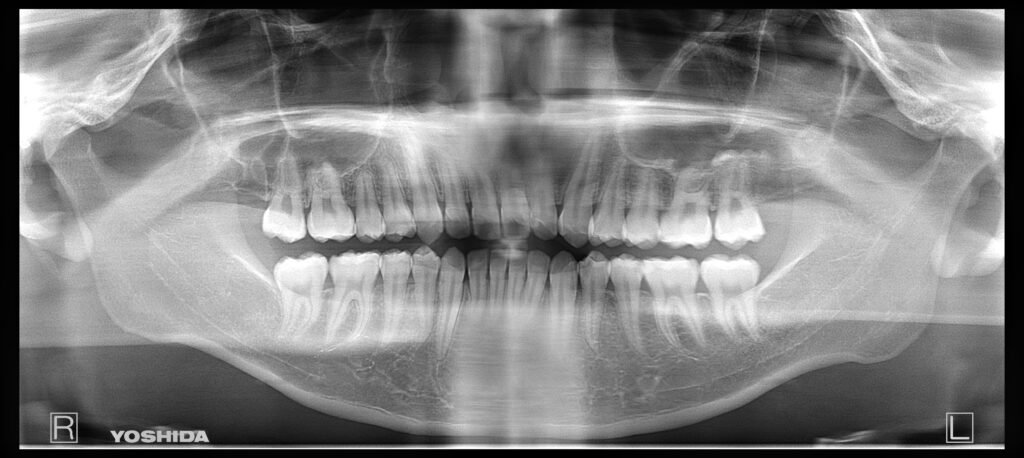

①親知らず抜歯後